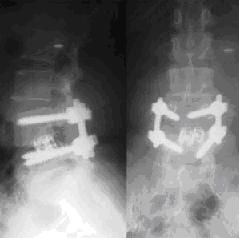

1.常規開放性手術(包括:半椎板切除、全椎板切除、經腹椎間盤手術) 2、椎間盤鏡手術

3、人工腰椎間盤置換

1、常規開放手術:

常規開放手術包括:全椎板切除、半椎板切除、經腹椎間盤手術、椎體融合術等。手術的目的是直接切除病變腰椎間盤髓核,解除神經根壓迫而達到治療目的。由於腰椎的特殊生理位置的限制,因此手術破壞了正常的腰椎骨生理結構,造成手術損傷大,易造成腰椎術後失穩,術後瘢痕組織粘連,術中誤傷神經根等一系列不良反應,所以多數病人懼怕手術,如何避免手術中造成的以上不良反應呢?這一直是醫學界的一大難題。